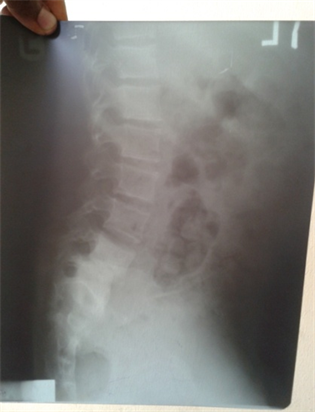

- X-Ray of the lumbosacral spine showed degeneration and collapse of the vertebrae and loss of joint spaces, involving L5, S1 and upper sacral spine, Spondylolisthesis of S1 and L5 was evident. (Figure 6 & Figure 7)

Figure 7. Lateral view of L5, S1 Compression Reproduced with permission.

Based on the history, positive mantoux test, Vertebral X-RAY and CXR results, a diagnosis of extra pulmonary TB (Scrofuloderma and Potts disease of the spine) was entertained. The viral warts were believed to be secondary to immunosuppression from TB. Decision was to commence full anti-Koch’s therapy immediately using Isoniazid (INH), Rifampicin, Pyrazinamide, Ethambutol according to NTBLCP guideline.